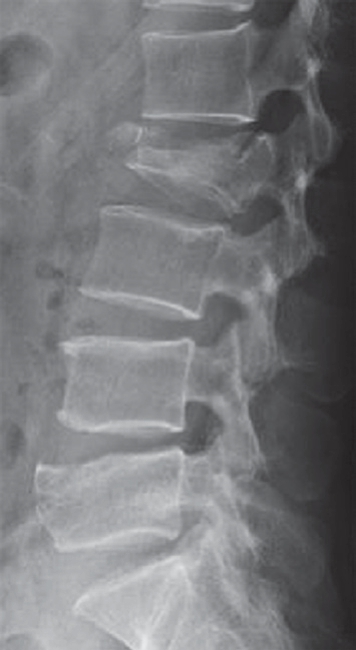

1.X线平片 X线平片表现为椎体前缘变短,侧位片椎体呈楔形,无骨折线,其上下椎间隙通常保持正常(图7-2-12)。

图7-2-12 X线侧位片显示压缩性骨折